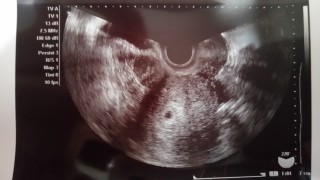

胎嚢のみ確認できました。 前回生理開始日から6週だと思っていたら「現在5週です」との事。 1週間前の診察では影も形も見えず、子宮外妊娠かも…と思っていたので安心しました。

3日前には確認できなかった胎嚢が、無事に5w0dで確認できました!大きさは不明ですが、外枠のメモリから判断して、4-5㎜かと思われます。次の診察は9日後です。無事に胎芽・心拍を確認できますように…!

最終月経開始日1/18。3/6に陽性。3/7胎嚢見えず。3/15に胎嚢確認、7ミリ。次は2週間後に診察!心拍確認できますように!